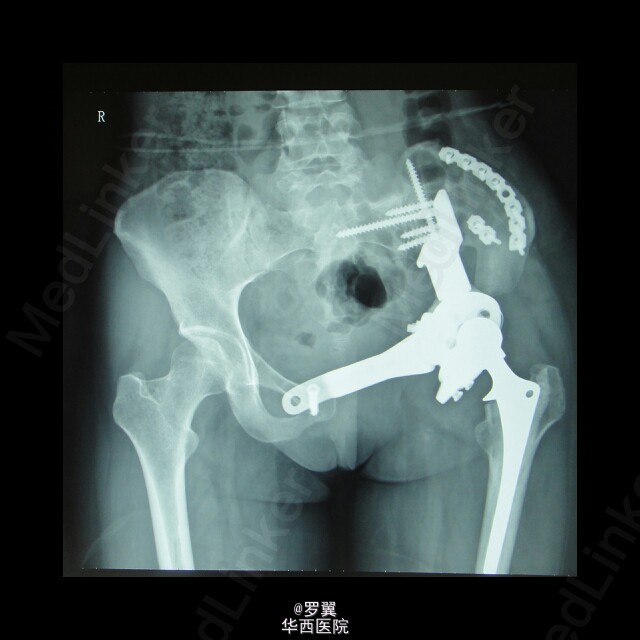

骨盆恶性肿瘤半骨盆假体置换术后髂骨断裂

患者23岁女性,骨盆恶性肿瘤半骨盆假体置换术后,进行髂骨保留并予钢板螺钉内固定,术后2年残留髂骨疲劳断裂。。